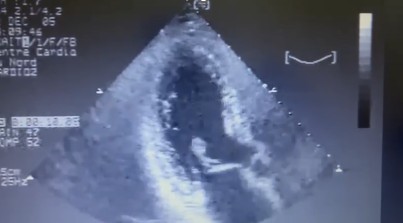

Ecocardiograma:

A: regurgitação mitral importante

B: Rápido movimento do músculo papilar com prolapso para átrio